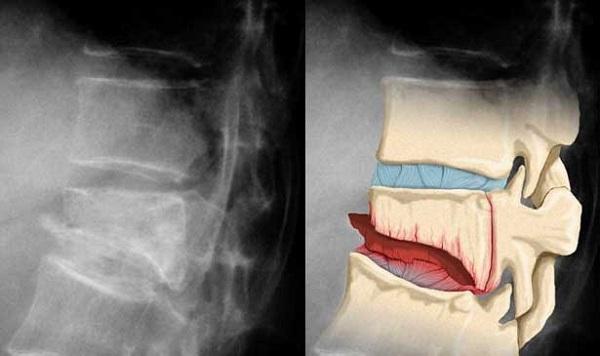

Компрессия и декомпрессия представляют собой два противоположных физических процесса. Первое явление связано с сжатием физического объекта, тогда как второе – с его растяжением. Оба этих процесса, при чрезмерном воздействии на организм, могут привести к повреждению структур объекта. Посмотрите на фото.

Когда человек сталкивается с проблемой, он часто задается вопросом, в чем разница между декомпрессионным и компрессионным переломом позвоночника. Основное отличие заключается в том, что при декомпрессионном переломе позвоночник подвергается растяжению, что приводит к повреждению мягких тканей и спинного мозга.

В случае компрессионного перелома происходит одновременное сжатие и сгибание одного или нескольких позвонков, в результате чего страдают не только мягкие ткани, но и костные структуры.

Рентгенография проводится в боковой и фронтальной проекциях, что позволяет хирургу оценить степень повреждения тела одного или нескольких позвонков. Для более точного определения состояния мягких тканей назначаются МРТ и КТ.